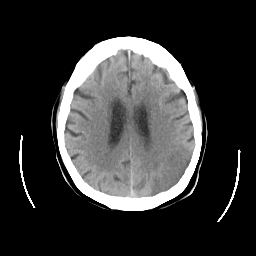

CT Study #2 -- Slice #19